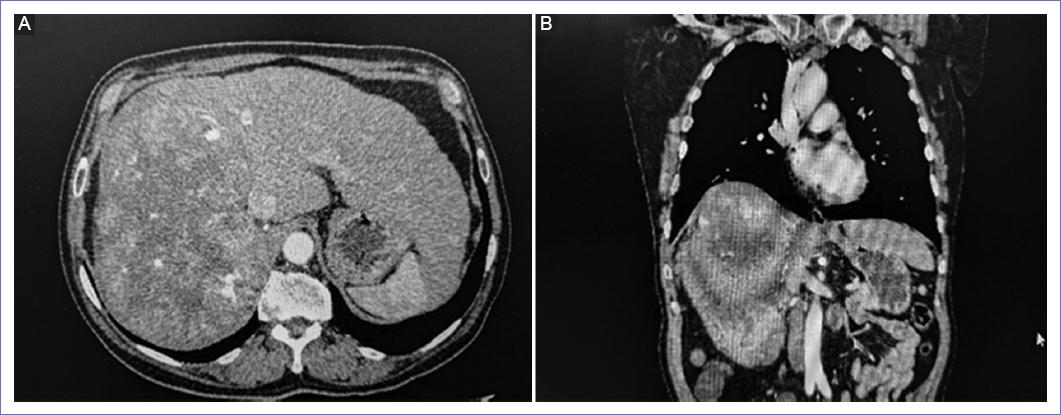

Se realizaron estudios de gabinete como tomografía de abdomen (Fig. 1) con imagen de aspecto quístico, irregular, bordes mal definidos, con importante neovascularización en segmentos IVa, IVb, V,VI, VII, de 17.5 x 13.3 x 19.9 cm que desplaza el contenido visceral.

Figura 1 A: tomografía axial de abdomen en fase contrastada tumor hepático lóbulo derecho. B: imágenes coronales por tomografía abdominal contrastada donde se evidencia tumor a nivel de hígado con elevación de hemidiafragma derecho.